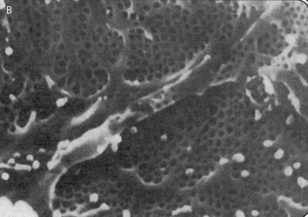

The epithelial lining of Bowman's capsule consists of a single layer of cells (podocytes), which rest on the basement membrane. The podocytes have large extensions or trabeculae, which extend out from the cell body and are embedded in the basement membrane surrounding a capillary. Small processes called pedicels extend out from the trabeculae and interdigitate extensively with the pedicels of adjacent trabeculae. This leads to the formation of slit pores, which control the movement of substances through the final layer of the filter. The podocytes have a well-developed Golgi apparatus, used to produce and maintain the glomerular basement membrane. Podocytes can also be involved in phagocytosis of macromolecules (Figs 2.1 and 2.2).

image image

Fig. 2.2 Electron micrographs showing the arrangement of podocytes and glomerular capillaries as seen from Bowman's capsule. (A) Processes of podocytes run from the cell body (cb) towards the capillaries where they ultimately split into foot processes (pedicels). (B) Inner surface of a glomerular capillary.

(From Koeppen BM, Stanton B, 1996. Renal physiology, 2nd edn. Mosby Year Book.)